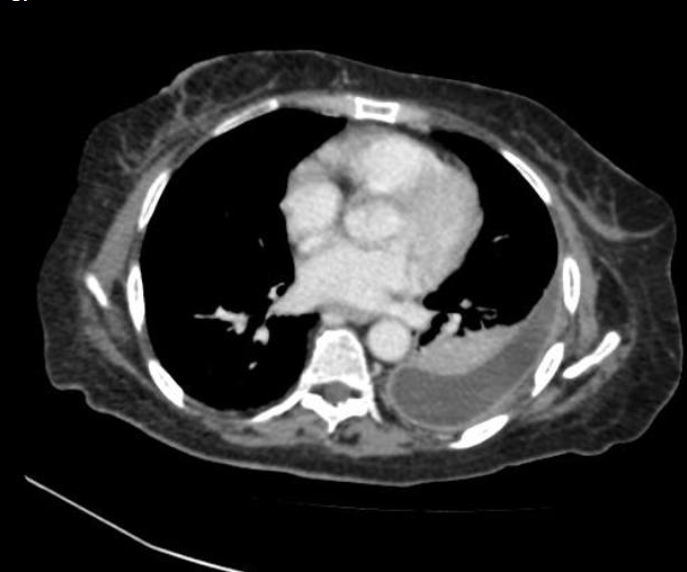

2 anos, masculino

Cisto de duplicação esofágico

Predleção por meninos; diagnosticados na infância

Em geral assintomáticos; podem provocar estridor

Mais comuns no esôfago distal; geralmente não comunicam com a luz do esôfago;

TC: Cisto com densidade de líquido, margens bem definidas que podem realçar com contraste; podem complicar com hemorragia, infecção: nível liquido, espessamento parietal.